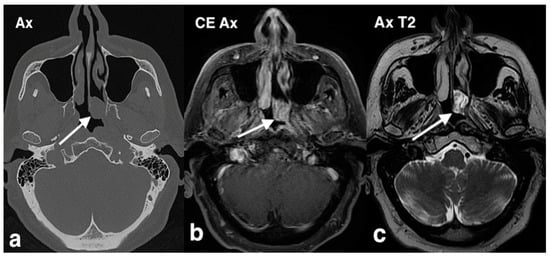

3.2.2. Chondromesenchymal Hamartoma

3.2.3. Ossifying Fibroma